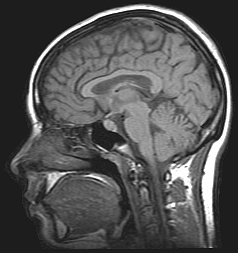

MRI-scan van de hersenen

MRI is gebaseerd op dezelfde technieken als de kernspinresonantie-spectroscopie zoals die in de chemische analyse wordt gebruikt. Om een MRI-scan te maken, wordt iemand in een MRI-scanner gelegd. Hierbij wordt de patiënt in een sterk, homogeen statisch magneetveld geplaatst (het B₀-veld). Protonen (waterstofkern) in lichaamsweefsel dat water of vet bevat geven een signaal af dat verwerkt kan worden tot een afbeelding. Eerst wordt er met elektromagnetische straling een trilling in het magneetveld opgewekt met precies de juiste resonantiefrequentie. De aangeslagen kernspins van de waterstofatomen zenden dan radiogolven uit, die worden gemeten met een spoel. De radiogolven kunnen zo worden afgesteld dat ze informatie geven over posities van bepaalde structuren in het lichaam door een gradiënt in de sterkte van het magneetveld te maken. De spoelen worden snel aan- en uitgezet, wat het kenmerkende rammelende geluid van een MRI-scan produceert. Het contrast tussen verschillende weefsels wordt onder andere bepaald door de hoeveelheid waterstof in het weefsel. Aangezien allerlei soorten weefsel verschillende waterstofdichtheden hebben kunnen dan details van de anatomie worden waargenomen.